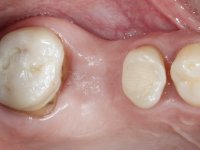

Teeth 17 and 16 were prepared for the fabrication of a 2-element Zr bridge. The impression was performed with a double mixing technique and a monolithic bridge in Zr was made in the laboratory. 4 years later, an abscess appeared in the apical area of tooth 26. It was decided to remove the bridge, remove the intra-radicular posts and retract the endodontic treatments of teeth 17 and 16. The removal of the bridge was carried out by making two cervical cavities. in the palatal area of the bridge and with a microluxator, disinsertion movements were performed. The intra-radicular posts were removed using fine drills and an ultrasound tip. The bridge was provisionally cemented and the patient was referred to a fellow endodontist for endodontic retreatment. After the retreatment, the intraradicular posts were placed again and the bridge was definitively cemented. One year later, a new abscess appears, possibly related to a root fracture. The bridge was sectioned between tooth 27 and 26 and tooth 26 was extracted and the crown of 27 was provisionally cemented. 3 months later, teeth 27 and 25 were prepared and a temporary bridge was made in dual polymerization resin. Then, an impression was made using the double mixing technique and a 3-element bridge in Zr was made in the laboratory. It was permanently cemented in the mouth with resin-reinforced glass ionomer cement.